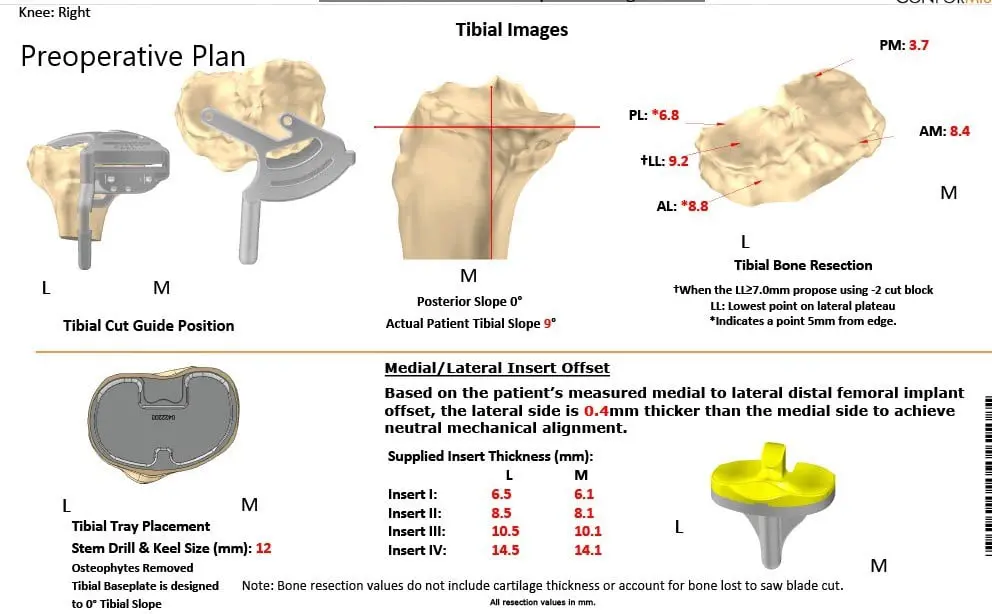

Further CT scan of the right knee was obtained prior to the surgery. The information was utilized to create a 3D model of the patient’s knee anatomy. Unique patient-specific implants were then constructed utilizing the information of anatomy and biomechanics. Custom disposable jigs and instruments were 3D printed to match patients’ natural anatomy of the knee. A customized preoperative plan was created for accurate bone cuts and biomechanics.

Complete Orthopedics patient-specific surgical plan for a right knee custom arthroplasty in an 83-year-old male.